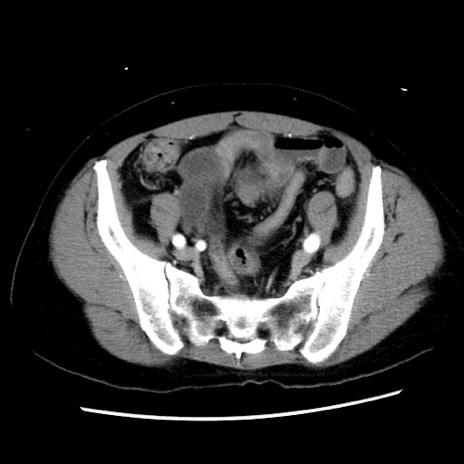

症例10(横断像)

【症例】 50歳代女性

【主訴】 腹痛

【現病歴】前日生レバーを食べた。今朝に排便あり。 昼前に突然発症の腹痛を生じ、当院救急外来を受診した。

【既往歴】 子宮筋腫にてで子宮全摘後

【身体所見】 意識清明、腹部:平坦、軟、下腹部やや左を中心に圧痛・反跳痛あり、筋性防御あり

【データ】WBC 7800、CRP 0.07